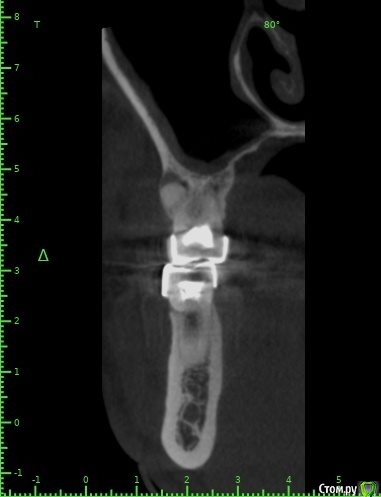

Raystom Опубликовано 20 февраля, 2021 Поделиться Опубликовано 20 февраля, 2021 Обратилась пациентка с неприятными ощущениями в области зубов 26, 27, во рту эти зубы показались мне темнее остальных, на КТ видна вот такая красота. Каков план лечения в таких ситуациях? Попробовать отделить пазуху от грануляций или просто удалить и после лечения ЛОРа идти на закрытие ОАС? Как после восстанавливать кость? И какие временные промежутки. Понимаю, что многие скажут при таких вопросах передать другим, но это не мой вариант. Мб есть литература по подобным случаям? Ссылка на комментарий

Raystom Опубликовано 20 февраля, 2021 Автор Поделиться Опубликовано 20 февраля, 2021 А что именно смущает? Что дефект с пазухой сообщается? Так закроете после удаления, ничего страшного. ЛОРу, имхо, там делать нечего пока еще.Недавно был подобный случай:12.png23.png22.png А вообще, судя по тем скринам, которые вы выложили, я бы пациента терапевтам показал для начала.Именно, что с пазухой. С терапевтами общались, при попытке препарирования зуб "мягкий", как кариозный судя по их словам Ссылка на комментарий

колесников Опубликовано 25 февраля, 2021 Поделиться Опубликовано 25 февраля, 2021 Киста сделала синуслифтинг,этот объём надо сохранить,колапол резорбируется быстро и через 3-6 мес останется 3мм,графт не скиснет,а созреет по форме дефекта,надо избежать вторичного инфицирования. Перекрыть вестибулярным лоскутом лунку не получится,раскрытие-инфицирование,боль,отёк,контрактура,смешение биотипа. Зачем? Можно нёбный мобилизовать или выбрать другой способ герметичного закрытия лунки Ссылка на комментарий

Raystom Опубликовано 26 февраля, 2021 Автор Поделиться Опубликовано 26 февраля, 2021 Киста сделала синуслифтинг,этот объём надо сохранить,колапол резорбируется быстро и через 3-6 мес останется 3мм,графт не скиснет,а созреет по форме дефекта,надо избежать вторичного инфицирования. Перекрыть вестибулярным лоскутом лунку не получится,раскрытие-инфицирование,боль,отёк,контрактура,смешение биотипа. Зачем? Можно нёбный мобилизовать или выбрать другой способ герметичного закрытия лунки. Запамятовал поинтересоваться. Чем лучше подкладывать в данном случае ксено, наподобие биооса или ауто, наподобие своей или шуроса? Ссылка на комментарий

колесников Опубликовано 26 февраля, 2021 Поделиться Опубликовано 26 февраля, 2021 Что предпочитаете. Если ксено,то с коллагеном. Я шурос использую Ссылка на комментарий